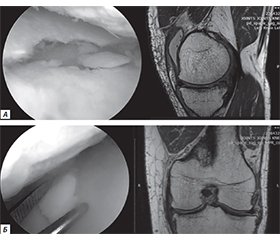

Актуальність. Фізична підготовка військовослужбовців відіграє ключову роль у забезпеченні ефективного виконання службових обов’язків, підвищення боєздатності підрозділів і збереження здоров’я особового складу. В умовах інтенсивної експлуатації організму під час бойових завдань, маршів, тактичних пересувань та тренувальних навантажень зростає ризик виникнення травм, зокрема опорно-рухового апарату. Особливо вразливими залишаються колінні суглоби, які зазнають значних динамічних навантажень. Незважаючи на відсутність впливу вогнепальних факторів, саме невогнепальні пошкодження часто призводять до тривалого лікування, втрати функціональності й тимчасової непридатності до служби. Мета дослідження: оцінити структуру, особливості й основні причини невогнепальних травм колінного суглоба у військовослужбовців Збройних сил України (ЗСУ) і проаналізувати вплив факторів ризику на їх виникнення. Матеріали та методи. У дослідженні проаналізовано результати обстежень магнітно-резонансної томографії та артроскопічних ревізій колінних суглобів 83 військовослужбовців-чоловіків віком 35–59 років (середній вік — 45,31 ± 7,48 року), які отримували лікування у відділенні важкої поліструктурної травми ДУ «Інститут травматології та ортопедії НАМН України» (м. Київ) у 2023–2025 рр. Результати. Отримані результати засвідчили переважання пошкоджень менісків (61 %), що, ймовірно, пов’язано з частими ротаційними навантаженнями та присіданнями у бойовому спорядженні. Розтягнення та розриви зв’язок становили 14 %, контузійні переломи, тріщини та хондральні пошкодження — 17 %, а хронічні дегенеративні зміни й запальні процеси — 8 % військовослужбовців ЗСУ. Висновки. Невогнепальні травми колінного суглоба становлять значну частку пошкоджень у військовослужбовців ЗСУ. Їх частота зумовлена високими фізичними навантаженнями, обмеженістю часу на адаптацію в умовах бойової обстановки та недосконалістю профілактичних заходів. Значне посилення уваги до профілактики, впровадження адаптованих тренувальних програм і своєчасна діагностика з ефективною реабілітацією здатні значно знизити ризики втрати працездатності.

Background. Physical fitness plays a crucial role in ensuring the adequate performance of military duties, enhancing the combat capability of units, and maintaining the health of service members. Under conditions of intensive physical exertion during combat missions, marches, tactical movements, and training, the risk of musculoskeletal injuries significantly increases. The knee joints are particularly vulnerable due to the high dynamic loads they endure. Although not caused by firearms, non-combat injuries often lead to prolonged treatment, functional impairment, and temporary unfitness for duty. The purpose was to assess the structure, characteristics, and primary causes of non-combat-related knee joint injuries among servicemen of the Armed Forces of Ukraine (AFU), and to analyse contributing risk factors. Materials and methods. This study analysed MRI scans and arthroscopic findings from surgical knee revisions in 83 male AFU servicemen aged 35–59 years (mean age — 45.31 ± 7.48 years), who received treatment at the Department of Severe Multistructural Trauma, SI “Institute of Traumatology and Orthopaedics of the NAMS of Ukraine” (Kyiv) in 2023–2025. Results. The data revealed a predominance of meniscal injuries (61 %), likely associated with frequent rotational loads and squatting in full tactical gear. Ligament sprains and ruptures accounted for 14 %, contusion fractures, fissures, and chondral damage for 17 %, while chronic degenerative and inflammatory joint changes made up 8 %. Conclusion. Non-combat knee injuries represent a significant proportion of musculoskeletal trauma among AFU personnel. Their prevalence is linked to intense physical exertion, limited adaptation time under combat conditions, and the lack of comprehensive preventive strategies. Strengthening prevention efforts, implementing adapted training protocols, and ensuring timely diagnosis and rehabilitation can significantly reduce the risk of disability and facilitate faster return to duty.